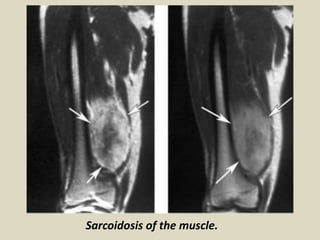

Sarcoidosis may also affect the muscles with myopathic or nodular type involvement.

On MR, sarcoid nodules show hypo-intense fibrotic central areas, with marginal

peripheral areas hyper-intense on T2-weighted images with enhancement after

gadolinium. These appearances may mimic a soft-tissue tumor. In the myopathic

type, the involved muscles demonstrate a high signal intensity on T2-weighted

images.

Sarcoidosis of the muscle.